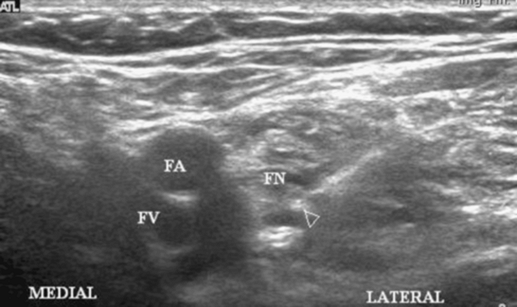

Sterile prep of the skin. The probe is placed just below the inguinal

crease with the probe oriented in the axial plane. The femoral artery

is identified and the hyperechoic nerve is identified lateral to the

artery (Fig. 39-3).

Figure 39-3. Femoral artery and hyperechoic nerve.